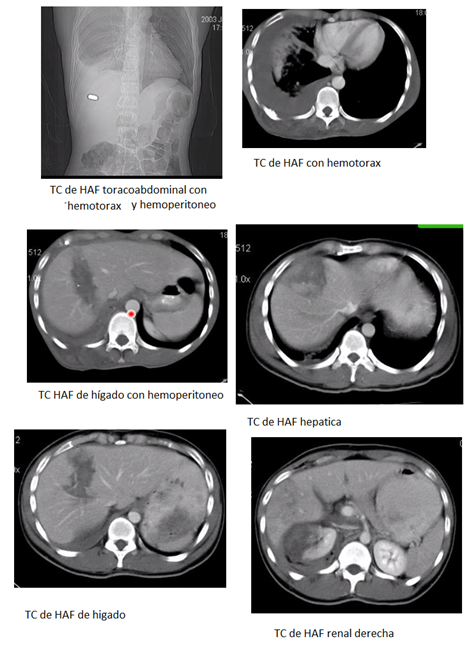

TRAUMA DE ABDOMEN POR HERIDA DE ARMA DE FUEGO (HAF)*:

Todas son quirúrgicas excepto:

- Heridas tangenciales que no ingresaron a peritoneo (entran y salen o se queda en solo músculo).

- Trayecto extraperitoneal (glúteo etcétera).

- Penetrante pero sin lesión de víscera.

- Penetrante con lesión de víscera maciza sin indicación de Cx por estar estable.

TCMC:

Con igual indicación de las HACP anteriores y en flanco o sea en HAF estable sin indicación de cirugía de emergencia, porque todas se consideran penetrantes (a no ser que la trayectoria del orificio de entrada y salida demuestre lo contrario).

Tiene S: 96.4%, E: 94.7%, VPP: 96.4 VPN: 94.7